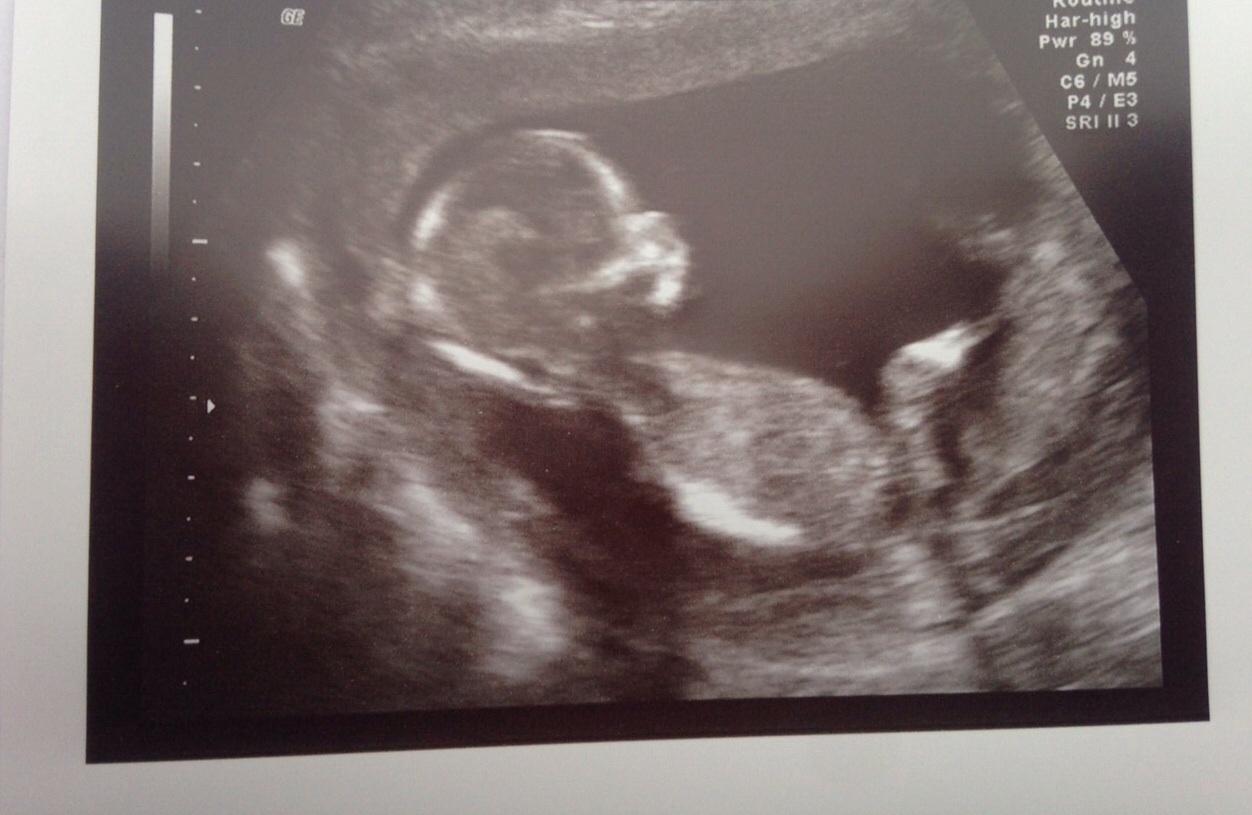

Hey, I'm new on here. Here's my 14week scan, any ideas on what baby could be?

Maaaaaaybe girly?? But I am not sure at all.

Also maybe girl. But no clear nub.

girl lean but not clear.

Maybe girl, but hard to see the nub.